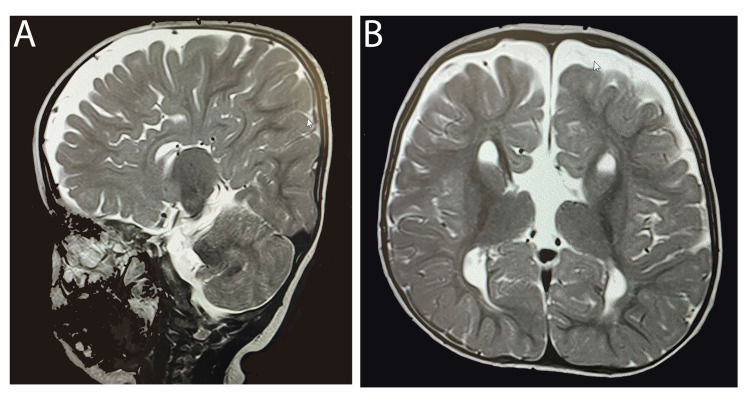

患者被 CI 委员会确定为双侧植入的候选者。 在三岁零五个月大时,进行了双侧同时人工耳蜗植入(HiRes™ Ultra #D 人工耳蜗,右 HiFocus™ SlimJ 电极和左 HiFocus™ Mid-Scala 电极,Advanced Bionics AG,加利福尼亚州,美国)。 术后 X 线显示 CI 阵列完全插入耳蜗内(图 2)。 手术后第二天开机,并给予两个 Naida CI Q70 声音处理器(Advanced Bionics AG,加利福尼亚州,美国)。

病例 2 的术后 X 线颞骨显示双耳人工耳蜗电极阵列完全插入